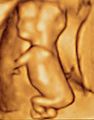

Prenatal development and sonograph images

Prenatal development is divided into two primary biological stages. The first is the embryonic stage, which lasts for about two months. At this point, the fetal stage begins. At the beginning of the foetal stage, the risk of miscarriage decreases sharply, all major structures including hands, feet, head, brain, and other organs are present, and they continue to grow and develop. When the fetal stage commences, a fetus is typically about 30 mm (1.2 inches) in length, and the heart can be seen beating via sonograph; the fetus bends the head, and also makes general movements and startles that involve the whole body. Brain stem activity has been detected as early as 54 days after conception, and the first measurable signs of EEG activity occur in the 12th week. Some fingerprint formation occurs from the beginning of the fetal stage.

One way to observe prenatal development is via ultrasound images. Modern 3D ultrasound images provide greater detail for prenatal diagnosis than the older 2D ultrasound technology. Whilst 3D is popular with parents desiring a prenatal photograph as a keepsake, both 2D and 3D are discouraged by the FDA for non-medical use, but there are no definitive studies linking ultrasound to any adverse medical effects. The following 3D ultrasound images were taken at different stages of pregnancy: